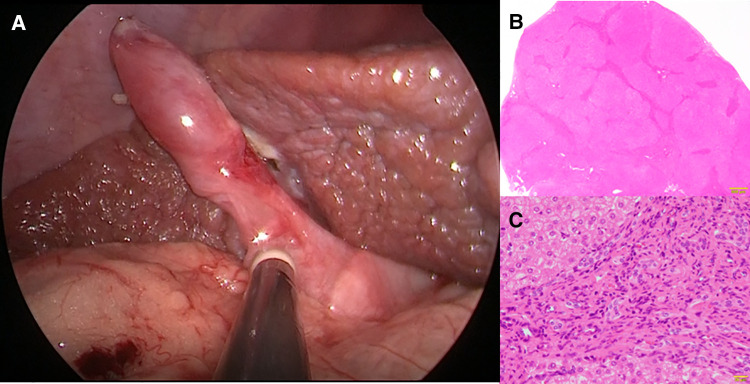

Following the improvement of the hepatic synthetic capacity (Alb, 4.0 mg/dl; AST, 82 IU/L; ALT, 78 IU/L; γ-GTP, 157 mg/dl; D-bil, 0.2 mg/dl; CHE, 232 IU/L; NH3, 75 μg/dl) (Table 1), we performed extrahepatic bile duct excision and hepaticojejunostomy laparoscopically (Supplementary File S2). Laparoscopic choledochal cyst excision was performed using five ports. Under general anesthesia, the patient was placed in the broad base position, and the operator stand to the right side of the patient. A 10-mm 30° laparoscope was inserted through an umbilical incision along with a trocar with a multichannel port device (E.Z Access/LAP-PROTECTOR minimini; Hakko Co., Ltd., Tokyo, Japan). Pneumoperitoneum was established with 8-mm Hg CO2 insufflation. Three additional trocars and a 2.4-mm needle-type grasper (Teleflex, Morrisville, NC, USA) were inserted into the right upper abdomen (operator’s left hand, 3.5 mm) and at the right side of the umbilicus (operator’s right hand, 5 mm), the left lateral abdomen (assistant’s left hand, 3.5 mm), and the left upper abdomen (assistant’s right hand, 2.4 mm). The dilated CBD was dissected and then taping was performed. After imaging the lower bile duct and confirming that the bile duct on the side of the pancreas was sufficiently detached, the lower bile duct was clipped and transected. Subsequently, after dissection and transection of the cystic duct, the hepatic duct just above the dilated common hepatic duct was transected. The jejunum was then extracted from the umbilical wound, and Roux-en Y jejunojejunostomy was performed. The mucosa and serosa of the opened hole was approximated using 6–0 absorbable sutures to secure hepaticojejunostomy. The jejunum was pulled up through the retro-colic route. Both the posterior and anterior walls were approximated using interrupted intracorporeal knot-tying with 5–0 absorbable sutures. Laparoscopic surgery was successfully performed along with liver biopsy. Histopathologically, the liver specimen showed chronic hepatitis and fibrosis (F3A2) based on the new Inuyama classification (ref. 14) (Figures 2A,B). F4 is defined as liver cirrhosis, but it presents clinical findings as disturbed consciousness with hyperammonemia and intraoperative findings as advanced liver fibrosis, and we clinically diagnosed to be almost equivalent to liver cirrhosis in the compensation stage. Biliary scintigraphy showed good bile excretion on postoperative day 15 (Supplementary File S3). The postoperative course was uneventful and the patient was discharged on the 23rd day after surgery.